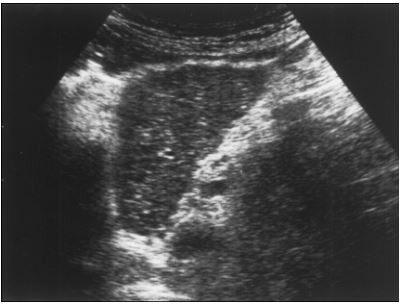

Mulher com 62 anos teve diagnóstico de hepatite C crônica e relata história de hemotransfusão em 1990. Trazia ultrassonografia de abdome (foto: plano longitudinal em região epigástrica) e elastografia hepática transitória (Fibroscan®) com resultado 9,5 kPa. Qual alternativa é correta sobre o caso?